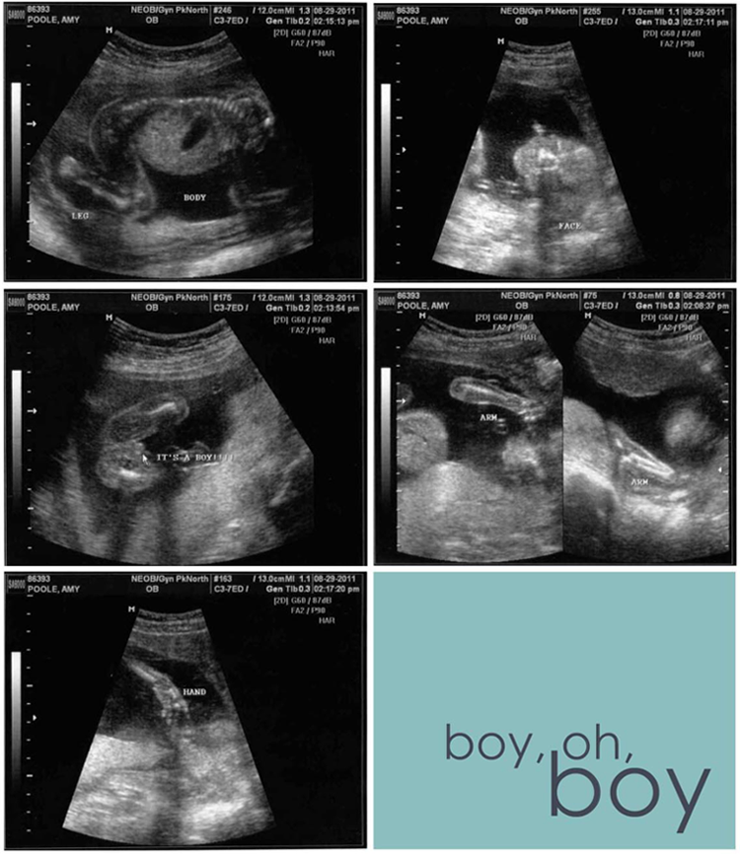

Well. Baby Poole was definitely moving. The ultrasound tech said it was squirming around in there quite a bit. She took lots and lots of measurements. Mostly I saw blobs on the screen that I didn't know what they were. Then I saw it. Baby Poole's spine. Finally a blob I could recognize. I looked over at Jeff and he had a huge grin on his face as he took pictures (or maybe video?) of the ultrasound screen.

The tech pushed and prodded my belly asking if it hurt. I said I was fine. She said that the baby was facing my back so it was hard to get a good look at what it was. "Oh crap," I thought. "We won't be able to find out its gender today." Then she got a shot from underneath its bum and I was pretty sure it looked like she was a boy. The tech confirmed my suspicions. Jeff laughed and looked at me. He came over and gave me a kiss. "It" was now "he." Even though Baby Poole was a tease, the tech was still able to get a shot of his squishy little face.

We met with Doc SlyCly for a few minutes. He told us our little boy looked like he was growing healthy and strong, and that he was right on track for my due date of January 18.

Baby Poole is a boy!